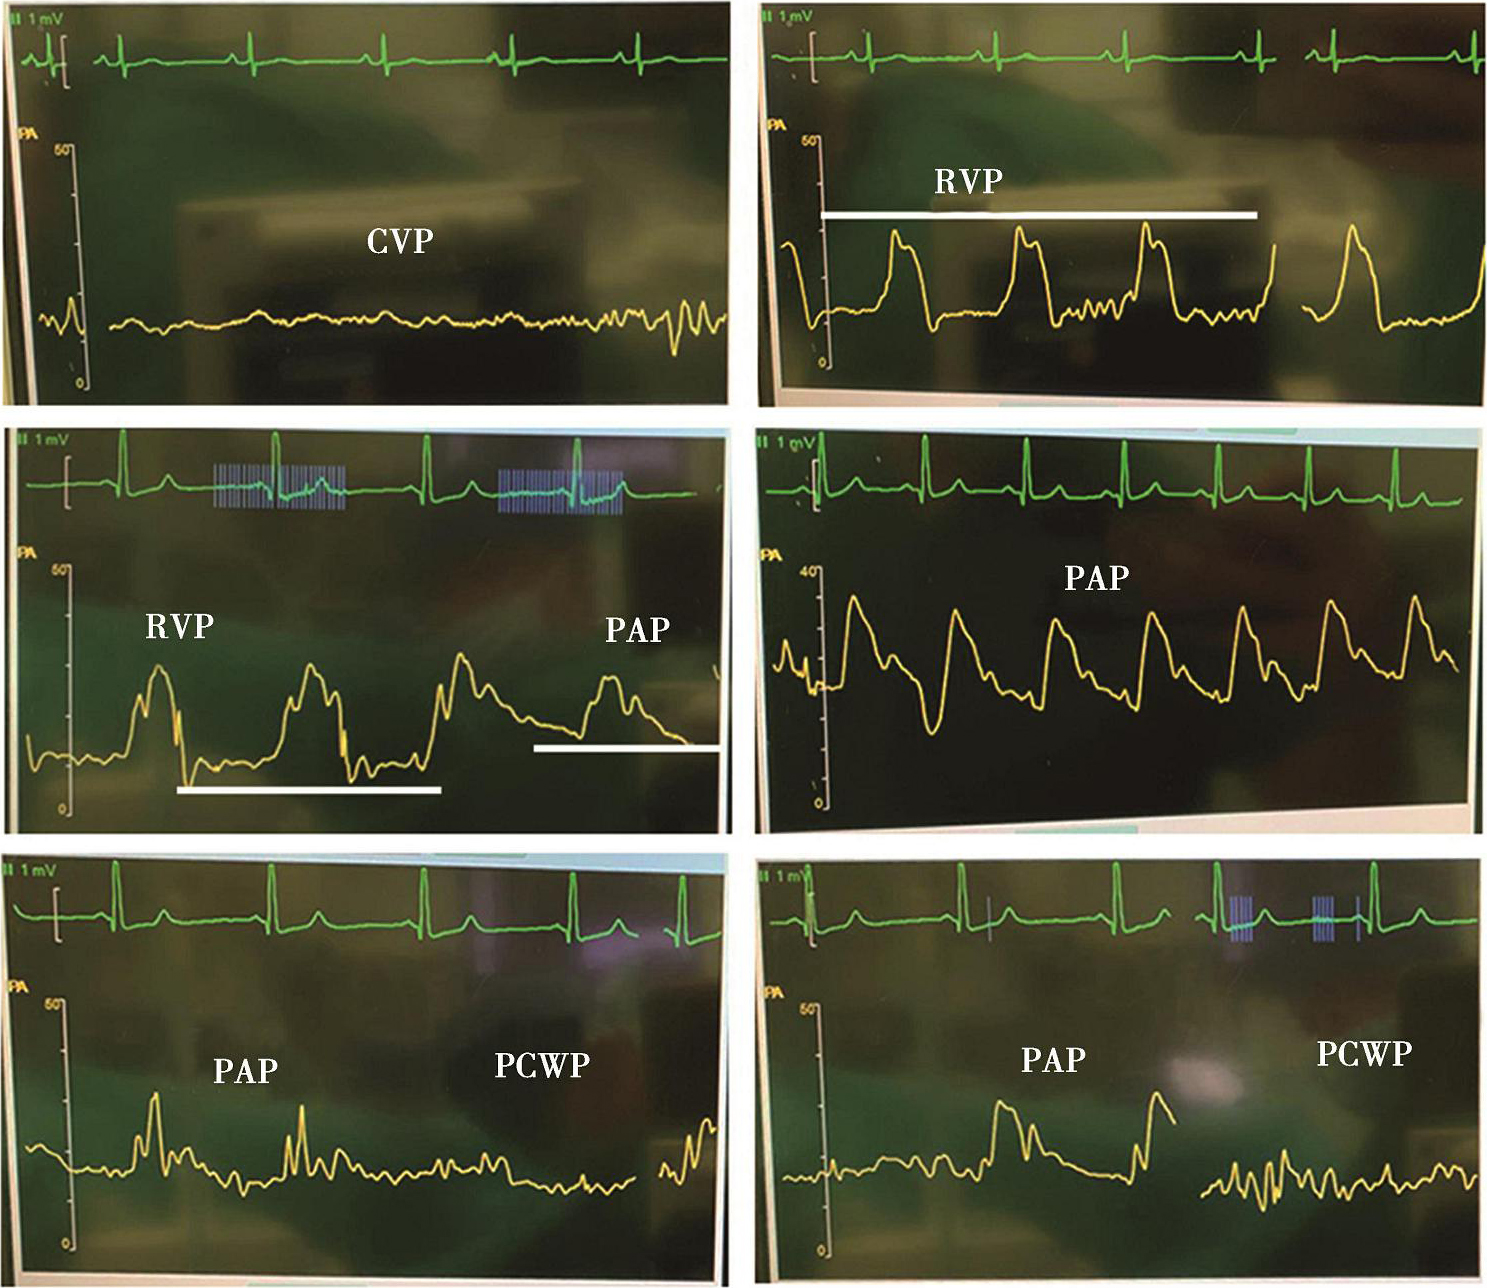

6.漂浮导管置入15~20cm后,将气囊充气并锁定。持续监测波形变化,以压力波形变化指导导管依次通过右心房、右心室、肺动脉并最终嵌顿(图3-1-4)。导管位于右心房时,压力波形与中心静脉压波形相同;导管进入右心室时会出现压力波形的急剧升高,舒张压一般低于10mmHg;导管进入肺动脉后,收缩压变化不大,但舒张压升高(大于10mmHg);当导管嵌顿后,压力波形再次转为PCWP波形,球囊放气后再次恢复为肺动脉压波形(图3-1-4)。

图3-1-4 肺动脉漂浮导管置入过程中波形变化

CVP.中心静脉压;RVP.右心室压;PAP.肺动脉压;PCWP.肺毛细血管楔压。